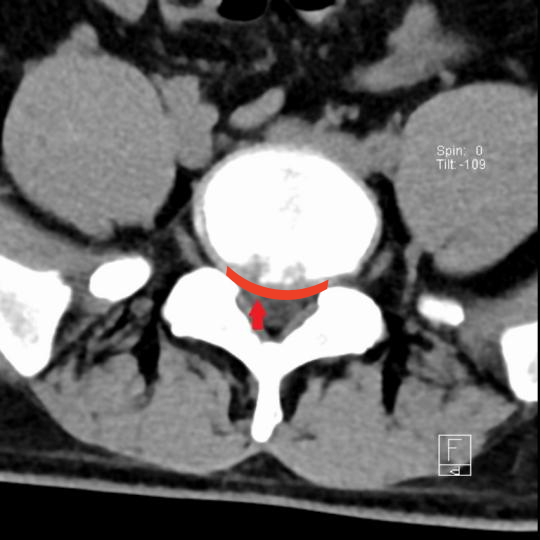

广医三院脊柱外科副主任医师王簕为小阳做了详细的检查,经CT、MRI检查后发现,小阳的腰5/骶1椎间盘膨出并偏右后方突出,右侧侧隐窝变窄,右侧神经根受压。